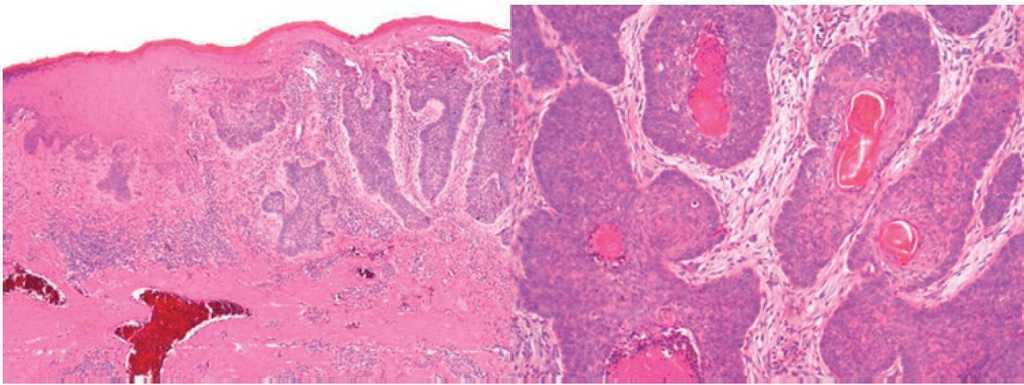

Figure 3. Malignant neoformation dependent on the basal layer of the epidermis with deep plane infiltration (limited to the subcutaneous cell tissue), multiple foci, and the phenomena of retraction and formation of attached structures consistent with solid, superficial, and multifocal basal cell carcinoma (with the palisade phenomenon, bland stroma, and peritumoral grooves).